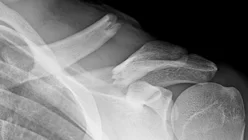

Clavicle Fracture: Management

- Surgical indications:

- Vascular compromise

- Open fractures

- Comminuted fractures with (Z-shaped) fragment

- Floating shoulder

- Severe displacement

- Tenting of the skin

- Patient’s preference

- (Athlete, active)